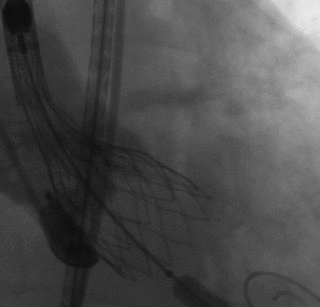

顺畅过弓

瓣膜开始释放